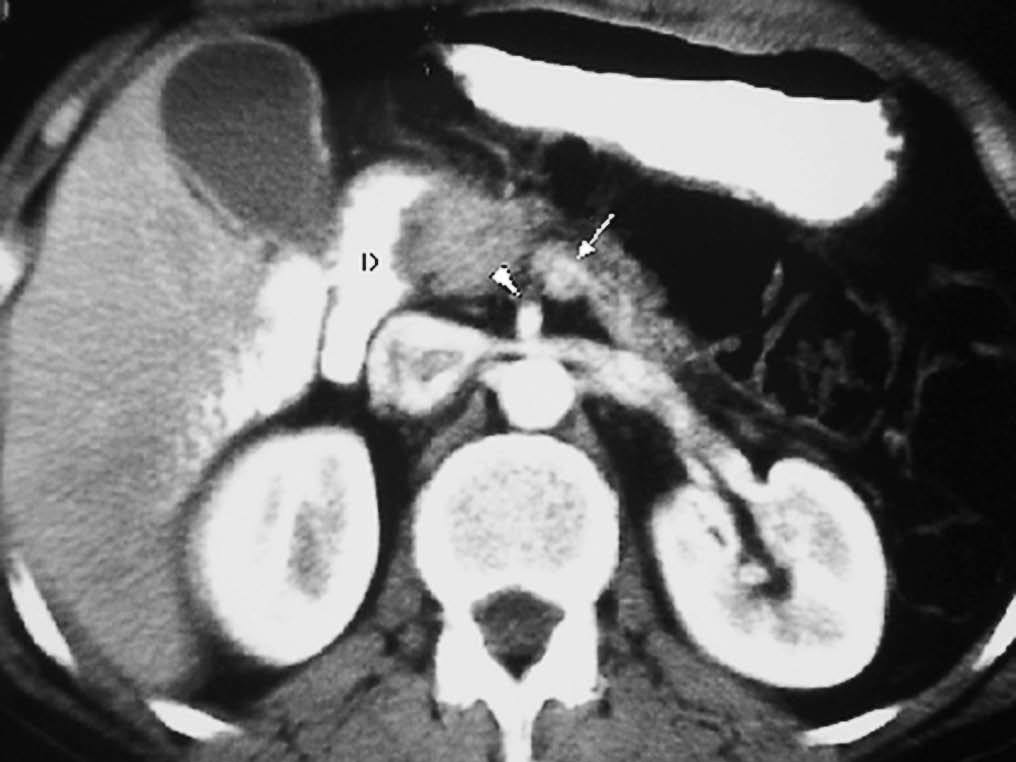

La forma más frecuente es la ausencia de rotación intestinal, que implica importantes alteraciones anatómicas valorables tanto en la ecografía como por la TC. Los principales hallazgos radiológicos son: alteración en la posición del duodeno, que no pasa entre la aorta y la arteria mesentérica superior (AMS); la localización en el hemiabdomen derecho de las asas de intestino delgado y en hemiabdomen izquierdo las de intestino grueso, y una verticalización o inversión de los vasos mesentéricos respecto a su posición normal, quedando la AMS a la derecha y la vena mesentérica superior (VMS) a la izquierda1,2 (fig. 1).

Fig. 1--Malrotación intestinal. (A) y (B) Tomografía computarizada con contraste oral e intevenoso mostrando inversión de la arteria mesentérica superior (AMS) (punta de flecha) y la vena mesentérica superior (flecha). La tercera porción duodenal (D) no cruza la línea media entre la aorta y la AMS, localizándose las asas de yeyuno a la derecha.